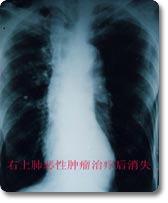

一、胸部X線檢查

本項檢查是發現腫瘤的最重要的一種方法。可通過X線透視,正、側位胸部X線攝片,發現塊影或可以腫塊陰影。進一步選用高電壓攝片、體層攝片、CT、磁共振顯像(MRI)、支氣管或血管造影等檢查,以明顯腫塊的形態、部位範圍及與心臟大血管的關係,了解肺門的縱隔淋巴結的腫大情況,支氣管阻塞、變形的程度以及肺癌有無轉移性病灶以提供診斷和治療的依據。肺癌的胸部X線檢查表現有如下幾種主要形式。

(一)中央型肺癌

多為一側肺門類圓形陰影,邊緣多多毛糙,有始有分葉表現;或為單側性不規則的肺門部腫塊,癌與專一性肺門或縱隔淋巴結融合而成的表現;也可以肺不張或阻塞性肺炎並存,形成所謂“S”型的典型肺癌的X線徵象。肺不張、阻塞性肺炎、預先性肺氣腫皆由於癌對氣管完全阻塞或部分阻塞引起的間接徵象。在體層攝片、支氣管造影可見到支氣管部分不規則增厚、狹窄、中斷或腔內腫物;視支氣管阻塞的不同程度可見有師尾狀、杯口狀況或者截平狀中斷。腫瘤發展至晚期侵犯鄰近器官和轉移淋巴結腫大,可見得有關肺門淋巴結腫大、縱隔塊狀影和氣管向健側移位;隆凸下淋巴結腫大可引起左右支氣管的壓跡、氣管分叉的高度變鈍和增寬以及食管中段局部受壓等;壓迫膈神經引起膈麻痹,可出現膈高位和矛盾運動;侵犯心包時,可引起心包積液等晚期徵象。